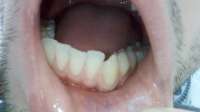

>>513868

Как и обещал. Забавно, в зеркале кажется не так криво.

Вчера делал панорамный снимок. Всё как >>513480 сказал, ортодонт взял его только посмотреть. Внимание, вопрос знатокам, ортодонт посмотрел на второй пикрелейтед и сказал, что зуб в котором штифт нужно переделывать - канал не полностью залечили, а так же второй зуб - там тоже проблема с каналом и что если ставить брекеты, то им обоим придет пизда. Когда это лечить не понятно, времени в обрез, завтра пойду к своему врачу который год-полтора назад мне эти зубы лечил, послушаю что скажет. В то, что она плохо сделала не хочется верить, но нужно быть реалистом.